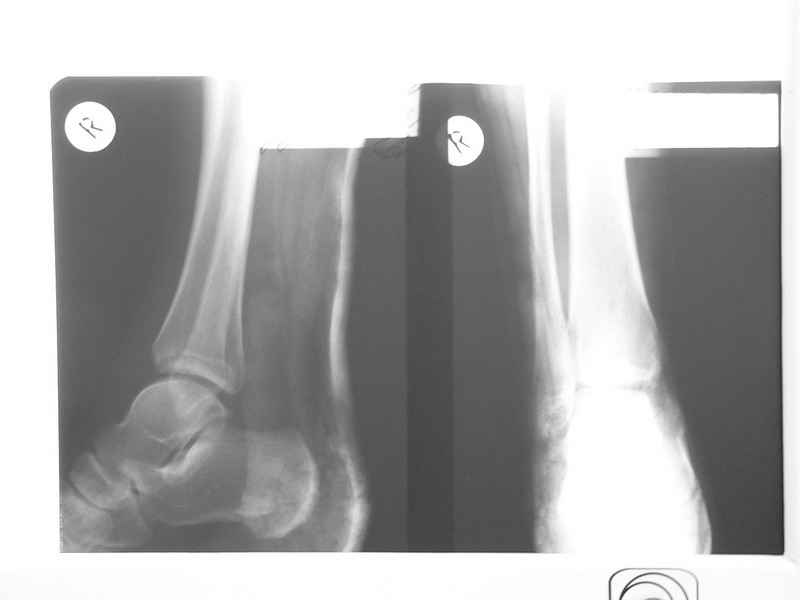

Уважаемые коллеги! Помогите определиться с тактикой лечения больной 50 лет! Травма в результате ДТП 1 января 2011г. открытый многооскольчатый перелом медиальной лодыжки левого голеностопного сустава со смещением. При поступлении в области медиальной лодыжки поперечная рана 5,0х1,0 см. сильно загрязнена, была выполнена ПХО. 05.01.2011г. сняты все швы по поводу нагноения раны, выполнена некрэктомия нежизнеспособных краев раны. На сегодня голеностопный сустав незначительно отечен, слегка болезнен при пальпации в области медиальной лодыжки. Температура тела нормальная, боли практически нет. Кровь спокойная. В области медиальной лодыжки имеется ранка округлой формы до 0,3 см., со скудным гнойным отделяемым (следы на салфетке после перевязки 1 раз в 2 дня). Посев из раны выполнить невозможно. На последних контрольных рентгенограммах признаки остеомиелита медиальной лодыжки? Помогите определиться с тактикой лечения: оперативное? Консервативное? С уважением Александр Белоконь!

4 недели после травмы - это еще пока открытый срастающийся инфицированный перелом, а не остеомиелит. Что касается рентгенограмм - в таком разрешении трудно оценить структуру кости.

Уважаемые коллеги! Прошу прощения за собственную невнимательность. У больной травма не 1 января 2011г., а 1 декабря 2010г., т.е. уже 2 месяца.

Прилагаю данные фистулогрфии. Основной вопрос, все же, лечить консервативно или оперативно? Если оперативно, то какой объем? А что если прийдеться резецировать всю медиальную лодыжку!?